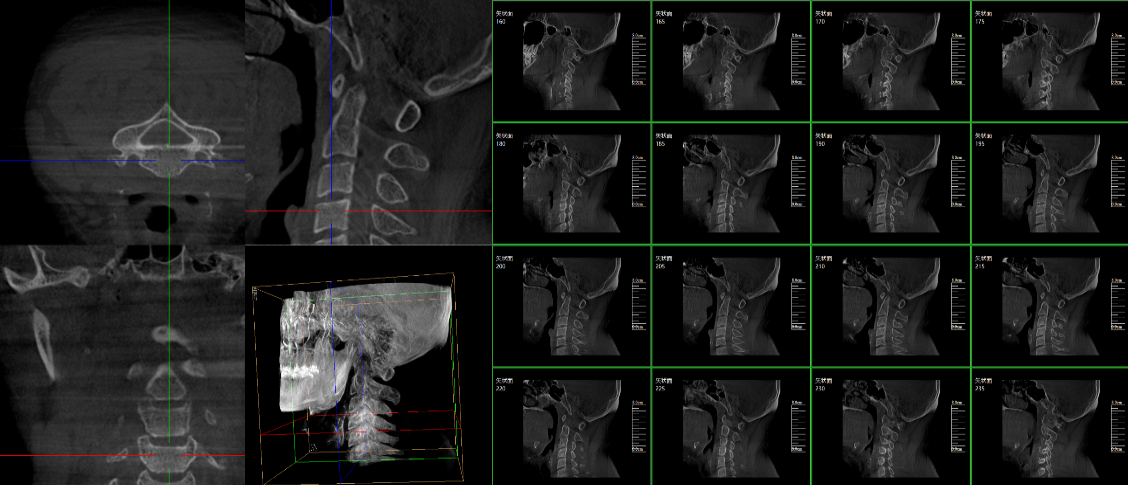

三維C臂,作為“術(shù)中CT”,能在術(shù)中快速地生成橫斷面、矢狀面、冠狀面和可旋轉(zhuǎn)的立體圖像,給術(shù)者提供360°無死角的觀察角度,全方位準(zhǔn)確判斷骨組織和植入物的情況,為手術(shù)的實(shí)施提供保障,極大提高手術(shù)成功率,減少并發(fā)癥概率。主要適用于骨科、脊柱外科、矯形外科、創(chuàng)傷骨科及手術(shù)室等。

普愛醫(yī)療三維C形臂具備術(shù)中實(shí)時(shí)三維成像,術(shù)中三維成像和橫斷面圖像提供多角度的手術(shù)診斷信息,輔助醫(yī)生進(jìn)行術(shù)中評(píng)估判斷,諸如骨折復(fù)位情況和內(nèi)植入螺釘?shù)某叽绾臀恢茫o助手術(shù)更好地完成;三維成像視野大,提供更大的術(shù)中三維成像視野,采集更多圖像信息,可一次拍全全段頸椎、全段腰椎、七節(jié)胸椎、雙側(cè)骶骼關(guān)節(jié)、股骨頭及單側(cè)盆骨等。如果您想了解更多普愛三維C形臂優(yōu)點(diǎn)及技術(shù)參數(shù),歡迎咨詢我們。